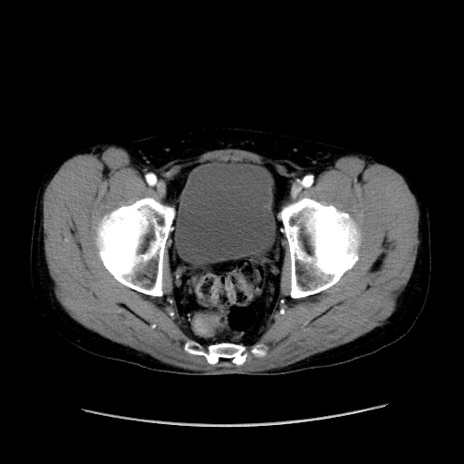

症例37(横断像)

【症例】40歳代 男性

【主訴】腹痛

【現病歴】4時間ほど前に電車に乗車中に臍部上より腹痛出現。徐々に増悪し起立困難となり、救急外来受診。生ものは数日食べていない。今朝お雑煮を食べた。

【身体所見】BT 36.8℃、BP 117/84mmHg、HR 91/min、SpO2 97%、苦悶様、腹部:臍上部広範囲圧痛あり、反跳痛±

【データ】WBC 8100、CRP 0.03